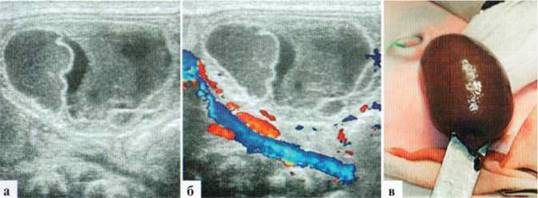

Относительно частой патологией у недоношенных девочек является паховая грыжа. В подавляющем большинстве случаев содержимым паховой грыжи у девочек является яичник, и риск возникновения его ишемических нарушений заставляет идти на оперативное лечение непосредственно по установлении диагноза. Необходимость в УЗИ возникает нечасто: для дифференциальной диагностики с воспалительными заболеваниями этой области, а также для оценки жизнеспособности яичника. При УЗИ удается достоверно визуализировать яичник, расположенный под кожей и подкожной клетчаткой, его фолликулы, место его похождения через паховый канал и сосуды, как собственно в яичнике, так и в его «ножке». Сохранение нормального строения яичника и сосудистого рисунка свидетельствует об отсутствии выраженных ишемических нарушений органа и о возможности проведения не экстренного, а срочного оперативного вмешательства (рис. 2.8). Целесообразно при УЗИ также визуализировать контралатеральный яичник, документально зафиксировать его наличие и структуру. Обычно яичник, находящийся в грыжевом мешке, несколько больше контралатерального за счет отека, даже при отсутствии гемодинамических нарушений. После операции, при сохраненной жизнеспособности яичника, эти изменения исчезают через 2—3 дня, яичники приобретают эхографически одинаковый вид.

Рис. 2.8. Паховая грыжа у новорожденной: а, б — левый яичник находится в паховой области в грыжевом мешке. Размеры — 22x13 мм, четко прослеживаются фолликулы до 5 мм в диаметре и стромальный компонент. Четко прослеживается сосудистый рисунок как в ткани яичника, так и в его «ножке», идущей через паховый канал